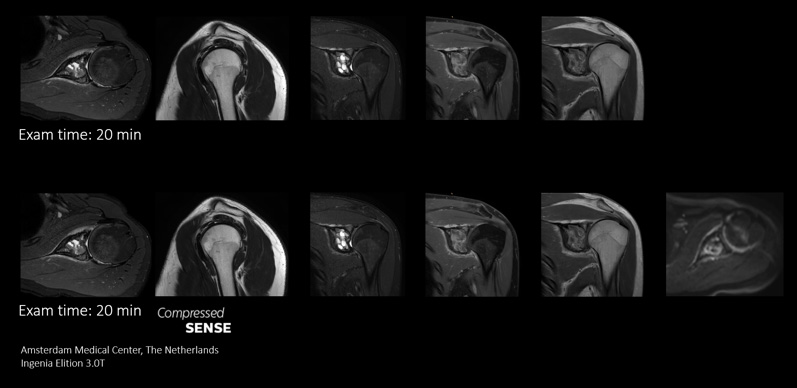

Compressed SENSE gibt MR-Abteilungen die Flexibilität, innerhalb des Zeitfensters für einen MR-Scan so viele relevante Daten wie möglich zu erfassen. Die Geschwindigkeit von Compressed SENSE ermöglicht die Aufnahme von zusätzlichen routinemäßigen und funktionellen Sequenzen für zuverlässigere diagnostische Informationen.

Dieser Fall demonstriert die Möglichkeit, zusätzliche Sequenzen zum selben Zeitfenster hinzuzufügen und so letztendlich die Diagnosesicherheit zu erhöhen. Neben klassischen TSE-Sequenzen ist im selben Zeitfenster auch eine funktionelle Sequenz mit diffusionsgewichteter Bildgebung möglich, die zusätzliche Informationen für die Diagnosestellung liefert.

Die schnelleren Scans mit Compressed SENSE erlauben uns die Aufnahme einer zusätzlichen Sequenz. Wir erhalten so hochwertige Bilder für zuverlässige Diagnosen.“

Sachi Fukushima, MTRA, Kurashiki Zentralkrankenhaus, Japan